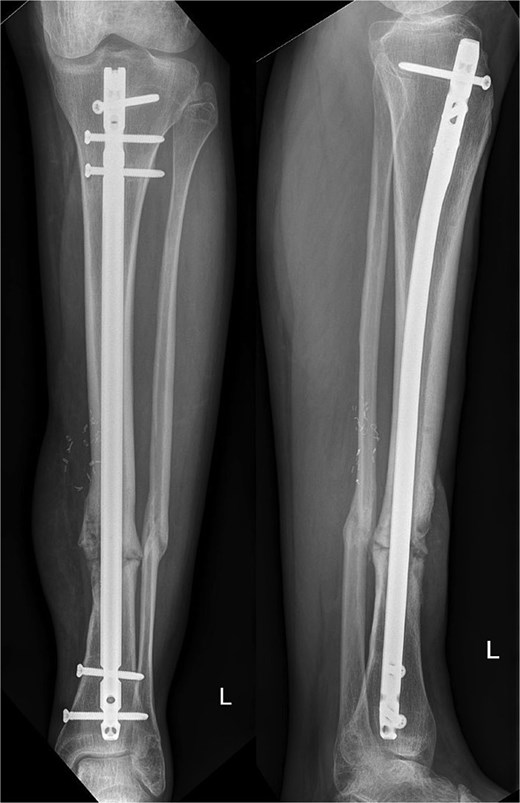

Ten months postoperatively, the patient was pain-free and demonstrated a normal gait pattern, associated with radiological signs of osseous consolidation (Fig. 3).

Our patient presented with an excellent result after 10 months without any restrictions and was completely pain-free. Our radiographic analysis demonstrated that no resorption occurred and no secondary movement of the graft (Fig. 3). Moreover, the even distribution of the graft was associated with no heterotopic bone formation or issues that would be related to donor site pathologies in distraction osteogenesis.